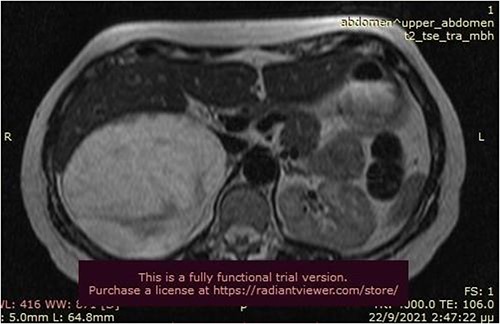

A 50-year-old woman was referred for surgical resection of a large right adrenal mass, which was incidentally found in an ultrasound scan performed for vague abdominal symptoms. Subsequently an abdominal MRI scan depicted a 16 × 15 × 6 cm right adrenal mass with characteristics suggestive of a myelolipoma, without evidence of vascular or periadrenal organ invasion (Figs 1 and 2). The patient underwent a comprehensive hormonal serum testing that confirmed a nonfunctioning adrenal mass. Because of the size of the lesion, an open operative approach was selected. Through a supraumbilical midline incision the mass was carefully dissected from the surrounding structures. It was adherent to the right kidney, the liver and the inferior vena cava without, however, compressing it. The harmonic scalper was used and clipping of the adrenal vasculature as appropriate. Intraoperatively, there was no adverse event. The specimen was removed intact and was sent for histological examination (Fig. 3). A silastic corrugated drain was inserted before closure of the laparotomy. The patient’s postoperative course was unremarkable and she was discharged on the third postoperative day. Histopathology revealed a lesion consisting predominantly of fatty tissue containing all types of hematopoietic stem cells and confirmed the diagnosis of myelolipoma (Figs 4 and 5).

MRI scan depicted a 16 × 15 × 6 cm right adrenal mass with characteristics suggestive of a myelolipoma (transverse plane).